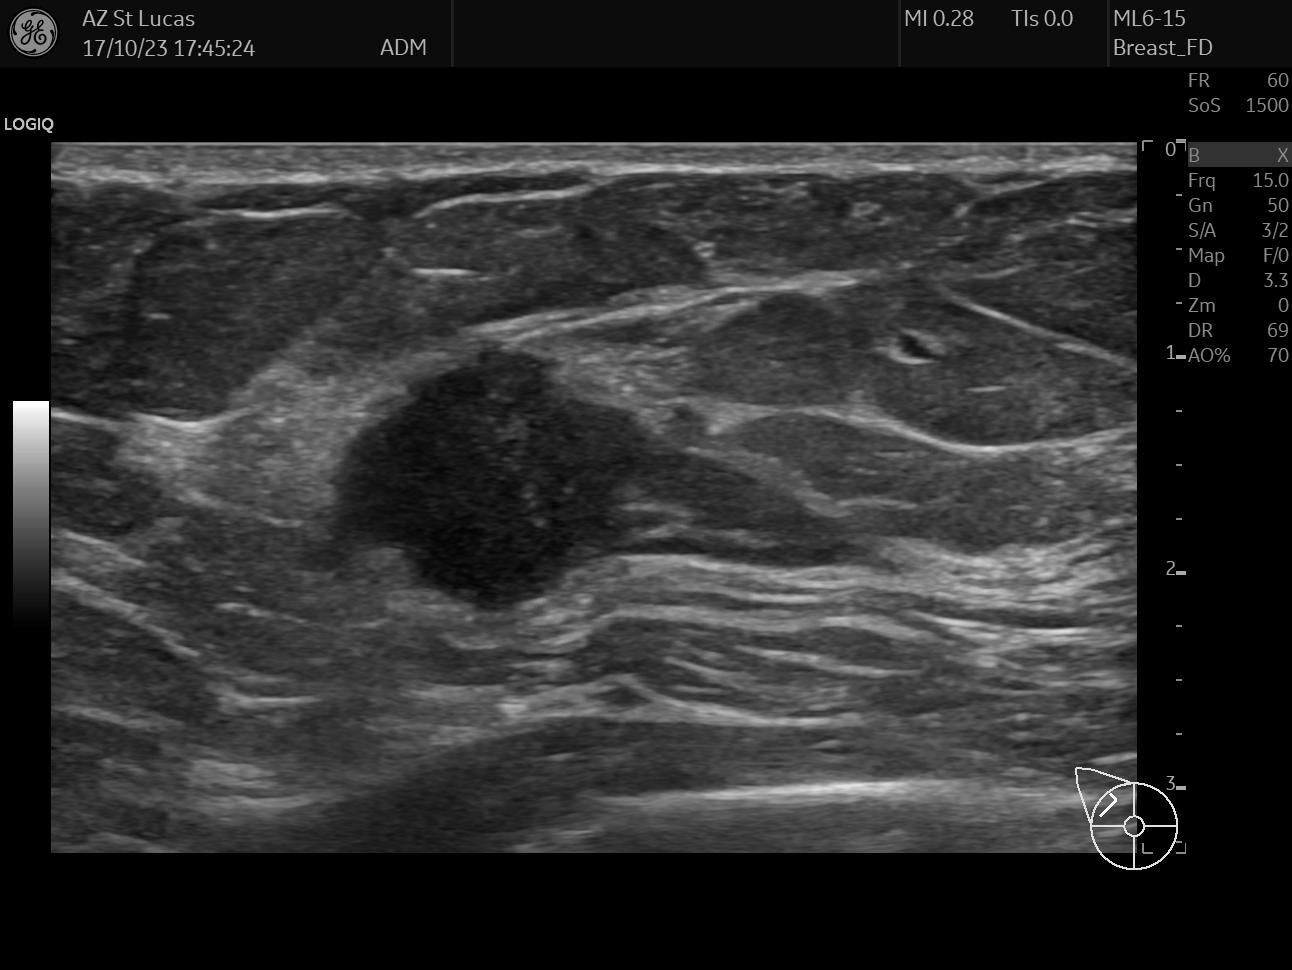

On October 17th 2023 I went to the hospital for an echography; the radiologist asked me almost immediately if they could perform a biopsy. So they stuck a needle in my breast and took out a few tissue samples. It was painful as hell and I ended up crying, confused, and trembling on the bed. The doctor asked me why I went alone for a check of this entity. Well, I didn’t know better, but there was my first lesson:

The data I chose for this day are two scans from the echography, they both clearly show the lesion; the second picture also shows the measurements the radiologist took.